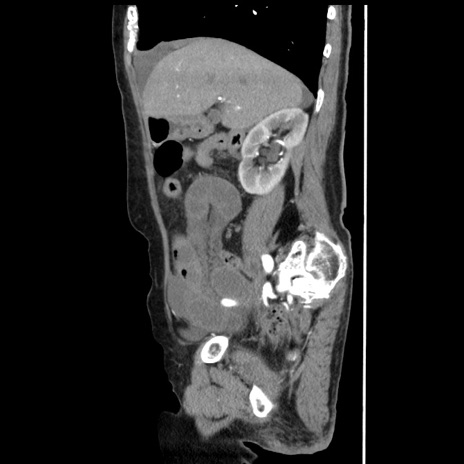

冠状断像

【症例】80歳代女性

【主訴】腹痛

【現病歴】8時間前から腹痛あり来院。

【既往歴】糖尿病、脂質異常症、子宮体癌にて子宮全摘術

【身体所見】意識清明・会話良好だが腹痛で苦悶様、全腹部にわたって反跳痛と圧痛あり

【データ】WBC 13600、CRP 0.14、LDH 224、CK 90